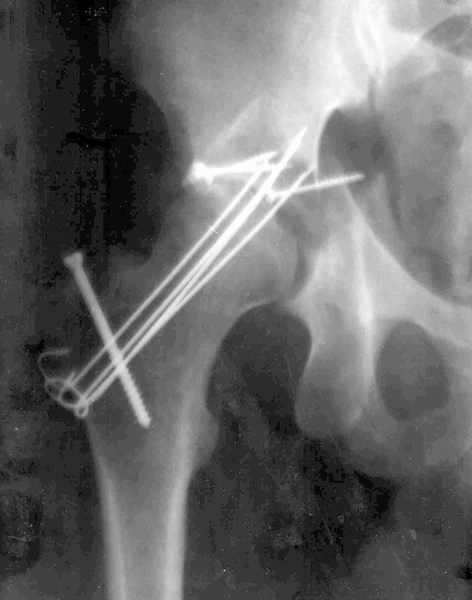

Мужчина 32 года, автотравма 6 недель назад. При поступлении был установлен диагноз "Ацетабулярный перелом". Вывих бедра не был установлен.

После установления вывиха бедра через 3 недели после травмы больному выполнена попытка открытой репозиции, остеосинтез вертлюжной впадины, Бедро фииксировано трансартикулярно спицами. После операции неврит седалищного нерва. В течение ещё 3-х недель после операции установлено что отломки не репонированы, вывих бедра не устранён (см. КТ и рентгенограмму), неврологической динамики нет. Возние вопрос о повторном оперативном вмешательстве по поводу чего разгорелись жаркие споры и сформировалось следующие мнения: 1. Тотальное эндопротезирование с цементной фиксацией чашки протезом "ЭСИ" (другого протеза нет) 2. Повторная открытая репозиция бедра с замещением дефектов вертлюжной впадины аутокостью с целью подготовки для последующего эндопротезирование. Предполагается фиксация тазобедренного сустава в послеоперационном периоде гипсовой повязкой или аппаратом внешней фиксации. Прошу высказать ваше мнение о тактике дальнейшего лечения пациента, о предложенных вариантах. Отдельный вопрос о возможности первичного тотального эндопротезирования при ацетабулярных переломах. (Лечащий врач настаивал перед первой операцией на выполнении тотального эндопротезирование с цементной фиксацией чашки через 3 недели после травмы)